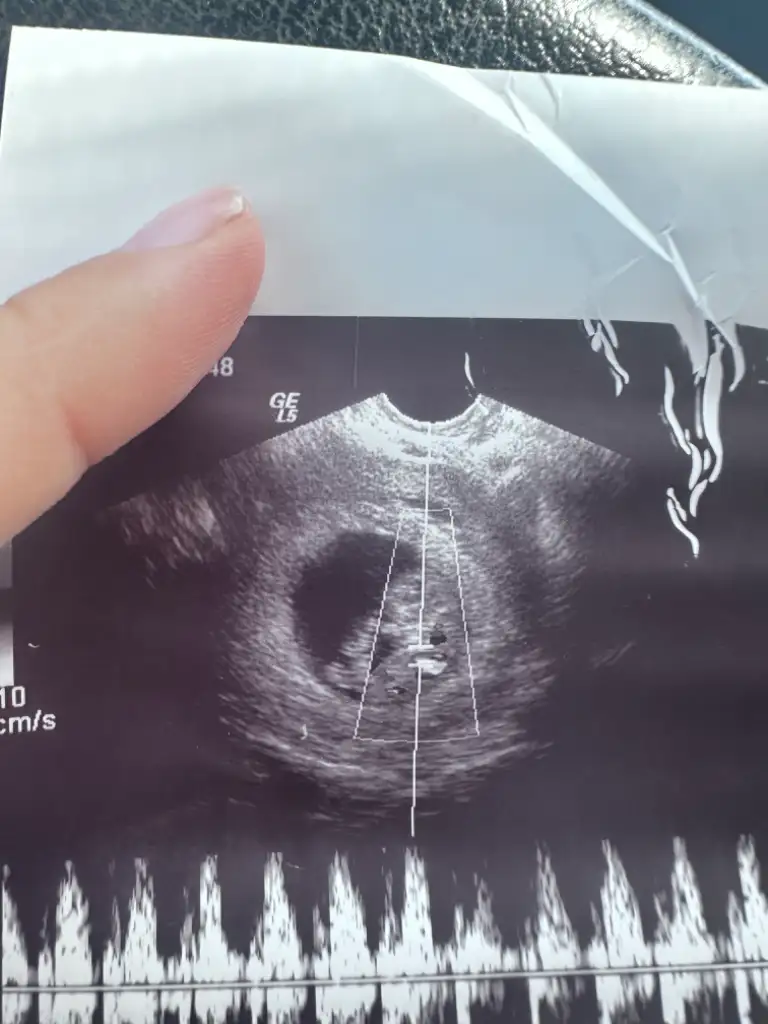

Canim ben en ileriyim galiba 12 haftadayiz ikiliyi bugün verdim normal muayenede ultrasonla burun ve ense kemigine bakıp ölçüsünü söylüyorlar ve sonra ac tok farketmez 1 tüp kan veriyosunuz bu kadar en kapsamlisi 2 li test bundanda kapsamlisi fetal dna testi. Fetal pahali bi test ama 2 li test devlette ücretsiz ikili sıkıntı gorurlerse zaten fetali ozman oneriyorlar